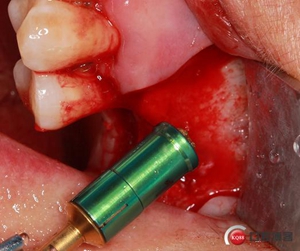

開(kāi)孔鉆上安裝1mm停止環(huán)。

開(kāi)窗位置鉆入1mm深度,未能穿透骨壁。

更換2mm停止環(huán)。

穿透上頜竇頰側(cè)骨壁,由于擴(kuò)孔鉆鉆頭特殊的設(shè)計(jì)形態(tài)

轉(zhuǎn)速雖快但不會(huì)穿破上頜竇膜。

使用水壓系統(tǒng),將1ml左右生理鹽水緩慢注入開(kāi)孔內(nèi)。

1ml水量便可將頰側(cè)上頜竇膜在還沒(méi)有開(kāi)窗剝離之前就已經(jīng)與上頜竇頰側(cè)骨壁剝離開(kāi)來(lái),所以此時(shí)再在開(kāi)孔處開(kāi)窗將不用再擔(dān)心會(huì)傷及上頜竇膜。用環(huán)切開(kāi)窗鉆,將種植機(jī)調(diào)成反轉(zhuǎn)模式、轉(zhuǎn)速調(diào)至200-500轉(zhuǎn)之間。